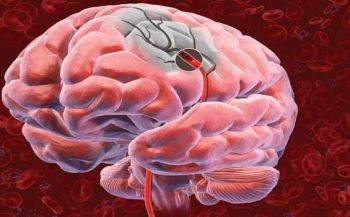

A trombose venosa representa a formação de um coágulo (trombo) que impede o fluxo normal do sangue no vaso sanguíneo, criando um grave problema para todo o sistema circulatório.

A TVP é a trombose que ocorreu em vasos profundos, geralmente dos membros inferiores. A doença também pode atingir pacientes que precisem ficar por longos períodos deitados ou foram submetidos a cirurgias que comprometam os movimentos. A doença, que pode ser assintomática, quando ocorrer, causa edema, dor, calor, vermelhidão e endurecimento dos músculos.